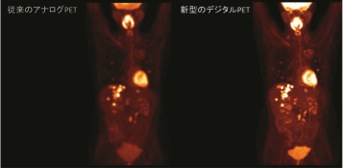

現在PET/CT装置に求められる3要素である分解能(空間的/時間的)、感度、定量性について全て2倍超(従来比)にスペックを改善し、画質/投与量/収集時間に妥協することなく臨床に求められるニーズに対してより戦略的なPET/CT検査を可能とし、近い将来の応用が待たれる新規PET製剤の基礎・臨床研究においてもインパクトのある貢献が期待される。

3.2倍超の感度、空間分解能、定量性向上による臨床への期待

デジタル

Si−PM検出器の搭載でTime-of-Flight方式の時間分解能は345ピコ秒まで短縮され、PETに必要な感度、空間分解能、定量性ともに(従来比)2倍超のスペックアップを達成している。特にPET画像は画質のみならず、SUV(Standard Uptake Value:標準取り込み値)に代表される定量値の精度が求められる。ダイナミックレンジの改善により従来PETでのSUV値に比べて精度の高い定量を追及した。今後、デジタルPET/CTでのSUV値の検証やデータの蓄積によって、悪性度の判定、治療方針の決定や治療効果判定のみならず未知の病態解明などへの貢献が期待される。